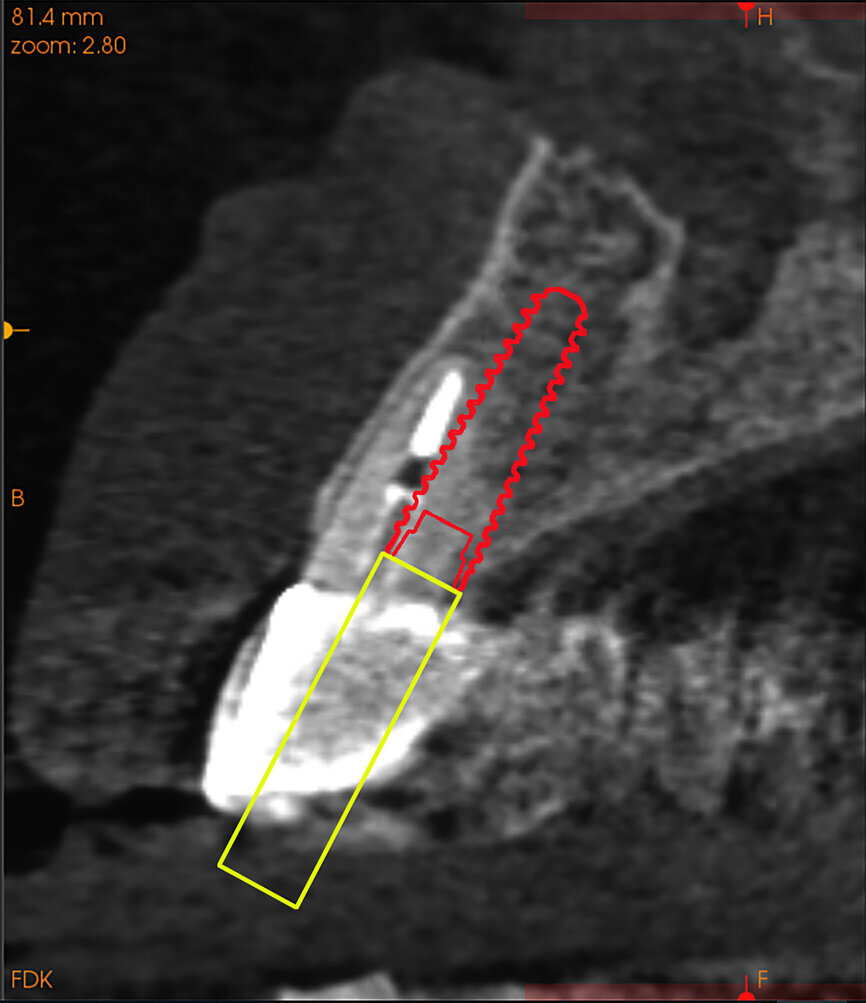

Fig. 14a:

The CBCT cross-sectional image revealed a favourable pre-op condition for a PET procedure.

Fig. 14b: Using the native Carestream 3D Imaging Software,

a simulated implant (red outline) and abutment projection (yellow outline) was positioned within the available bone to avoid the root fragment.

A 62-year-old male patient presented with a hopeless prognosis for a post fracture in the left central incisor requiring extraction (Figs. 12a & b). The preoperative periapical radiograph revealed an existing implant supporting a metal–ceramic restoration for the adjacent region #11 (Fig. 13). The CBCT (CS 9600, Carestream Dental) cross-sectional image revealed a favourable preoperative condition relating to the trajectory of the endodontically treated root to the alveolus for a PET procedure (Fig. 14a). Using the native Carestream 3D Imaging software, a simulated implant and abutment projection was positioned within the available bone to avoid the root fragment (Fig. 14b).